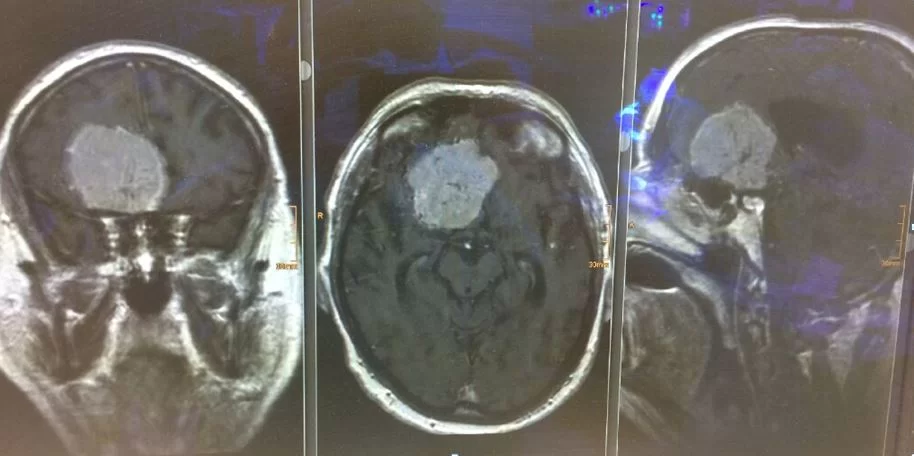

Ο απεικονιστικός έλεγχος με μαγνητική τομογραφία ανέδειξε ευμεγεθες οσφρητικό μηνιγγίωμα.

Διενεργήθη δεξιά υπερκόγχιος κρανιοτομία (τομή στο φρύδι) και ολική εξαίρεση της βλάβης.

Η ιστολογική εξέταση ανέδειξε μηνιγγίωμα WHO I.